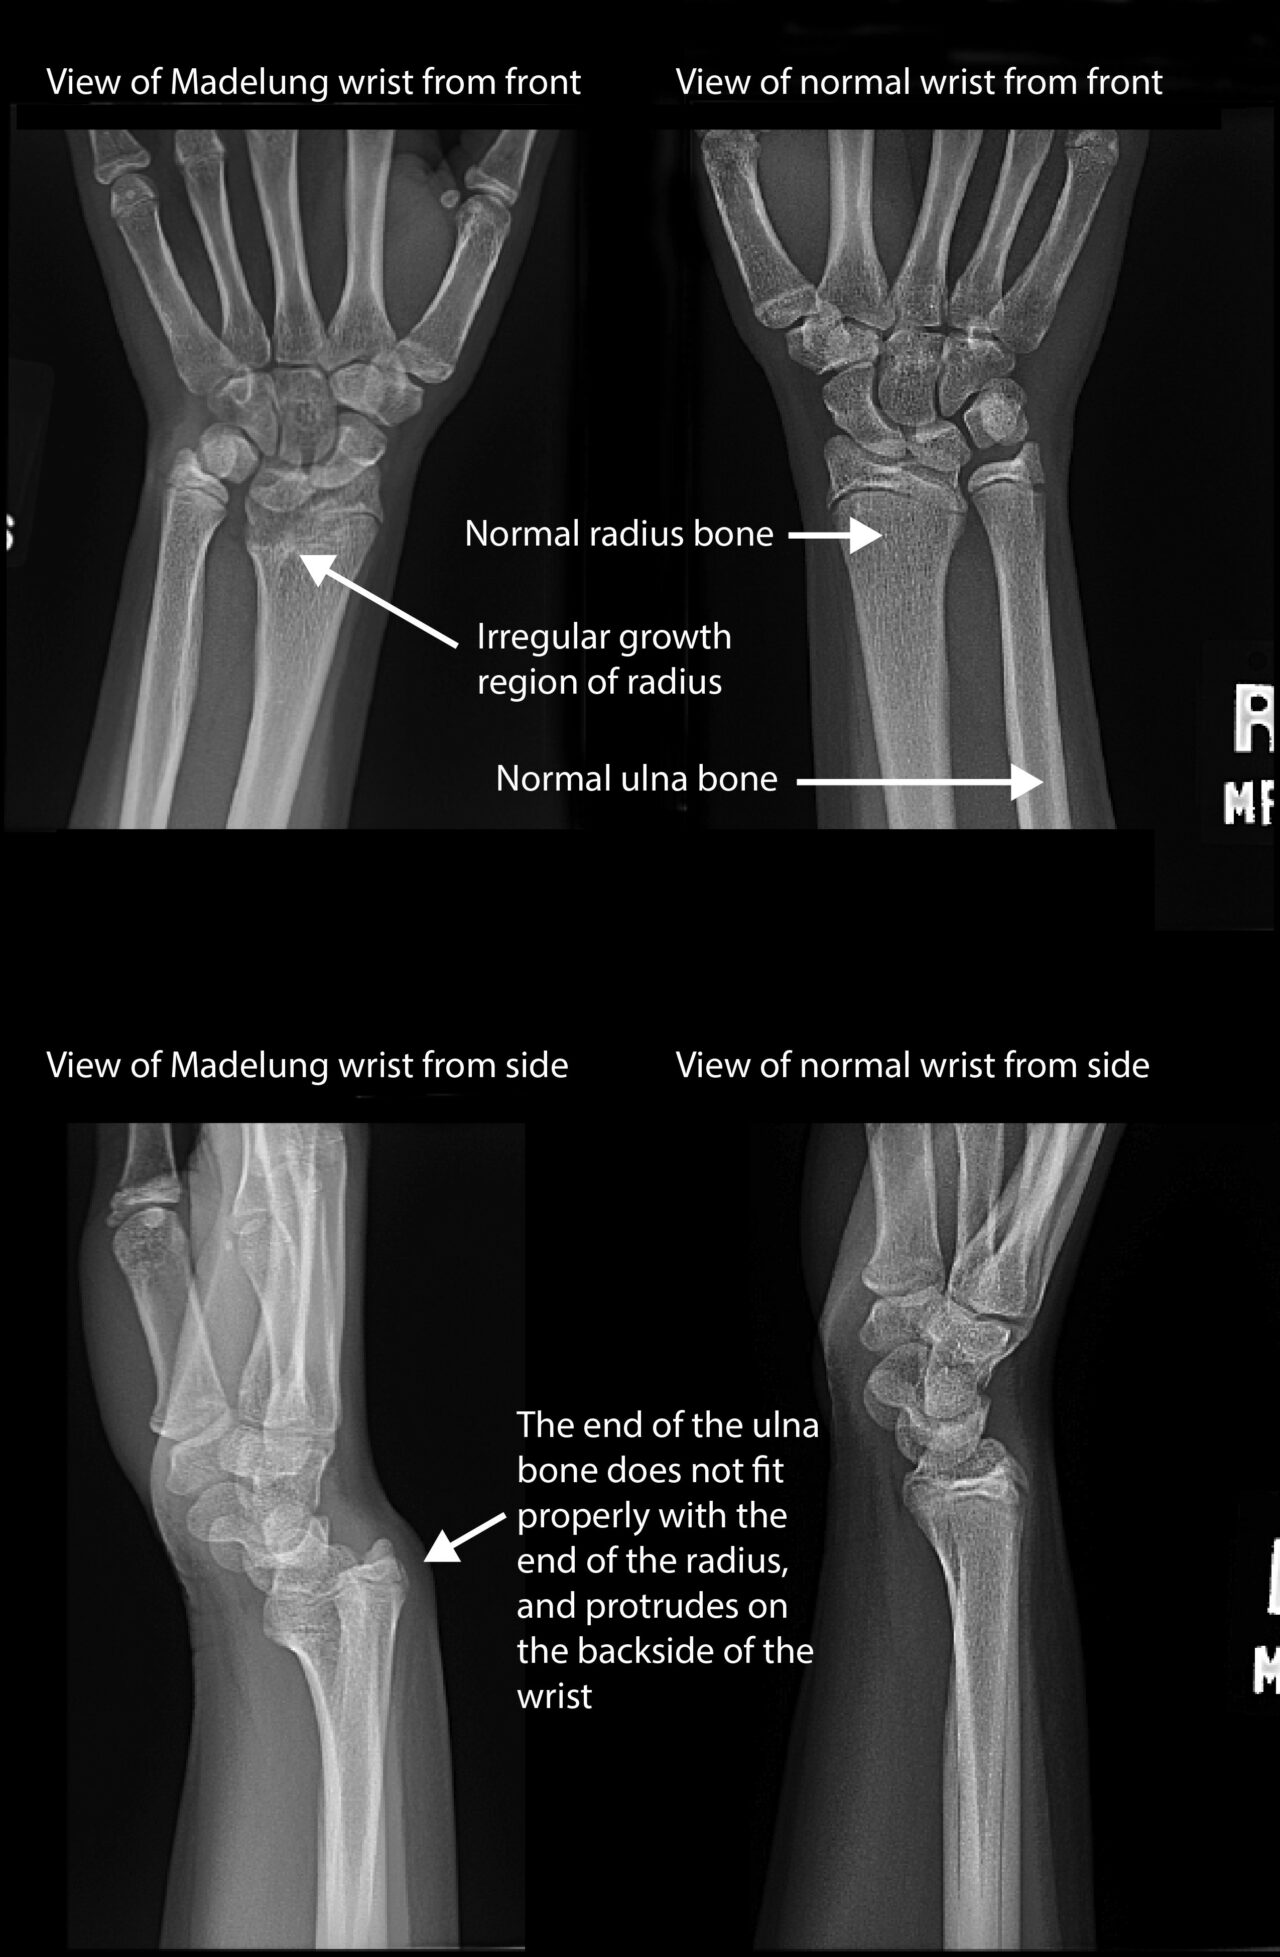

Radius Bone Deformity Madelung’s deformity is a rare arm condition that affects the growth plate of the radius, a bone in the forearm. Madelung deformity is a distal radius condition producing a deficiency in the volar ulnar corner that frequently causes wrist pain and cosmetic deformity (see. The radius is a long bone, one of the four types of bone in the body. The diaphysis is hollow, with space inside called the medullary cavity. The shaft is known as the diaphysis and the end of a long bone is called an epiphysis. As a child grows, this abnormal growth results in a misalignment where the two. The vast majority of pediatric radial and ulnar shaft fractures can be managed with closed treatment. A distal radius fracture is a break in the part of the bone closest to your wrist. Madelung's deformity is a congenital dyschondrosis of the distal radial physis that leads to partial deficiency of growth of the distal radial physis. A radius fracture, sometimes called a radial fracture, is a break of this bone. Madelung’s deformity is a rare arm condition that affects the growth plate of the radius, a bone in the forearm. A long bone is a dense, strong bone characterized as being longer than it is wide. Your doctor may refer to it as.

Madelungs Deformity Boston Children's Hospital Radius Bone Deformity A long bone is a dense, strong bone characterized as being longer than it is wide. Madelung’s deformity is a rare arm condition that affects the growth plate of the radius, a bone in the forearm. Madelung's deformity is a congenital dyschondrosis of the distal radial physis that leads to partial deficiency of growth of the distal radial physis. The. Radius Bone Deformity.